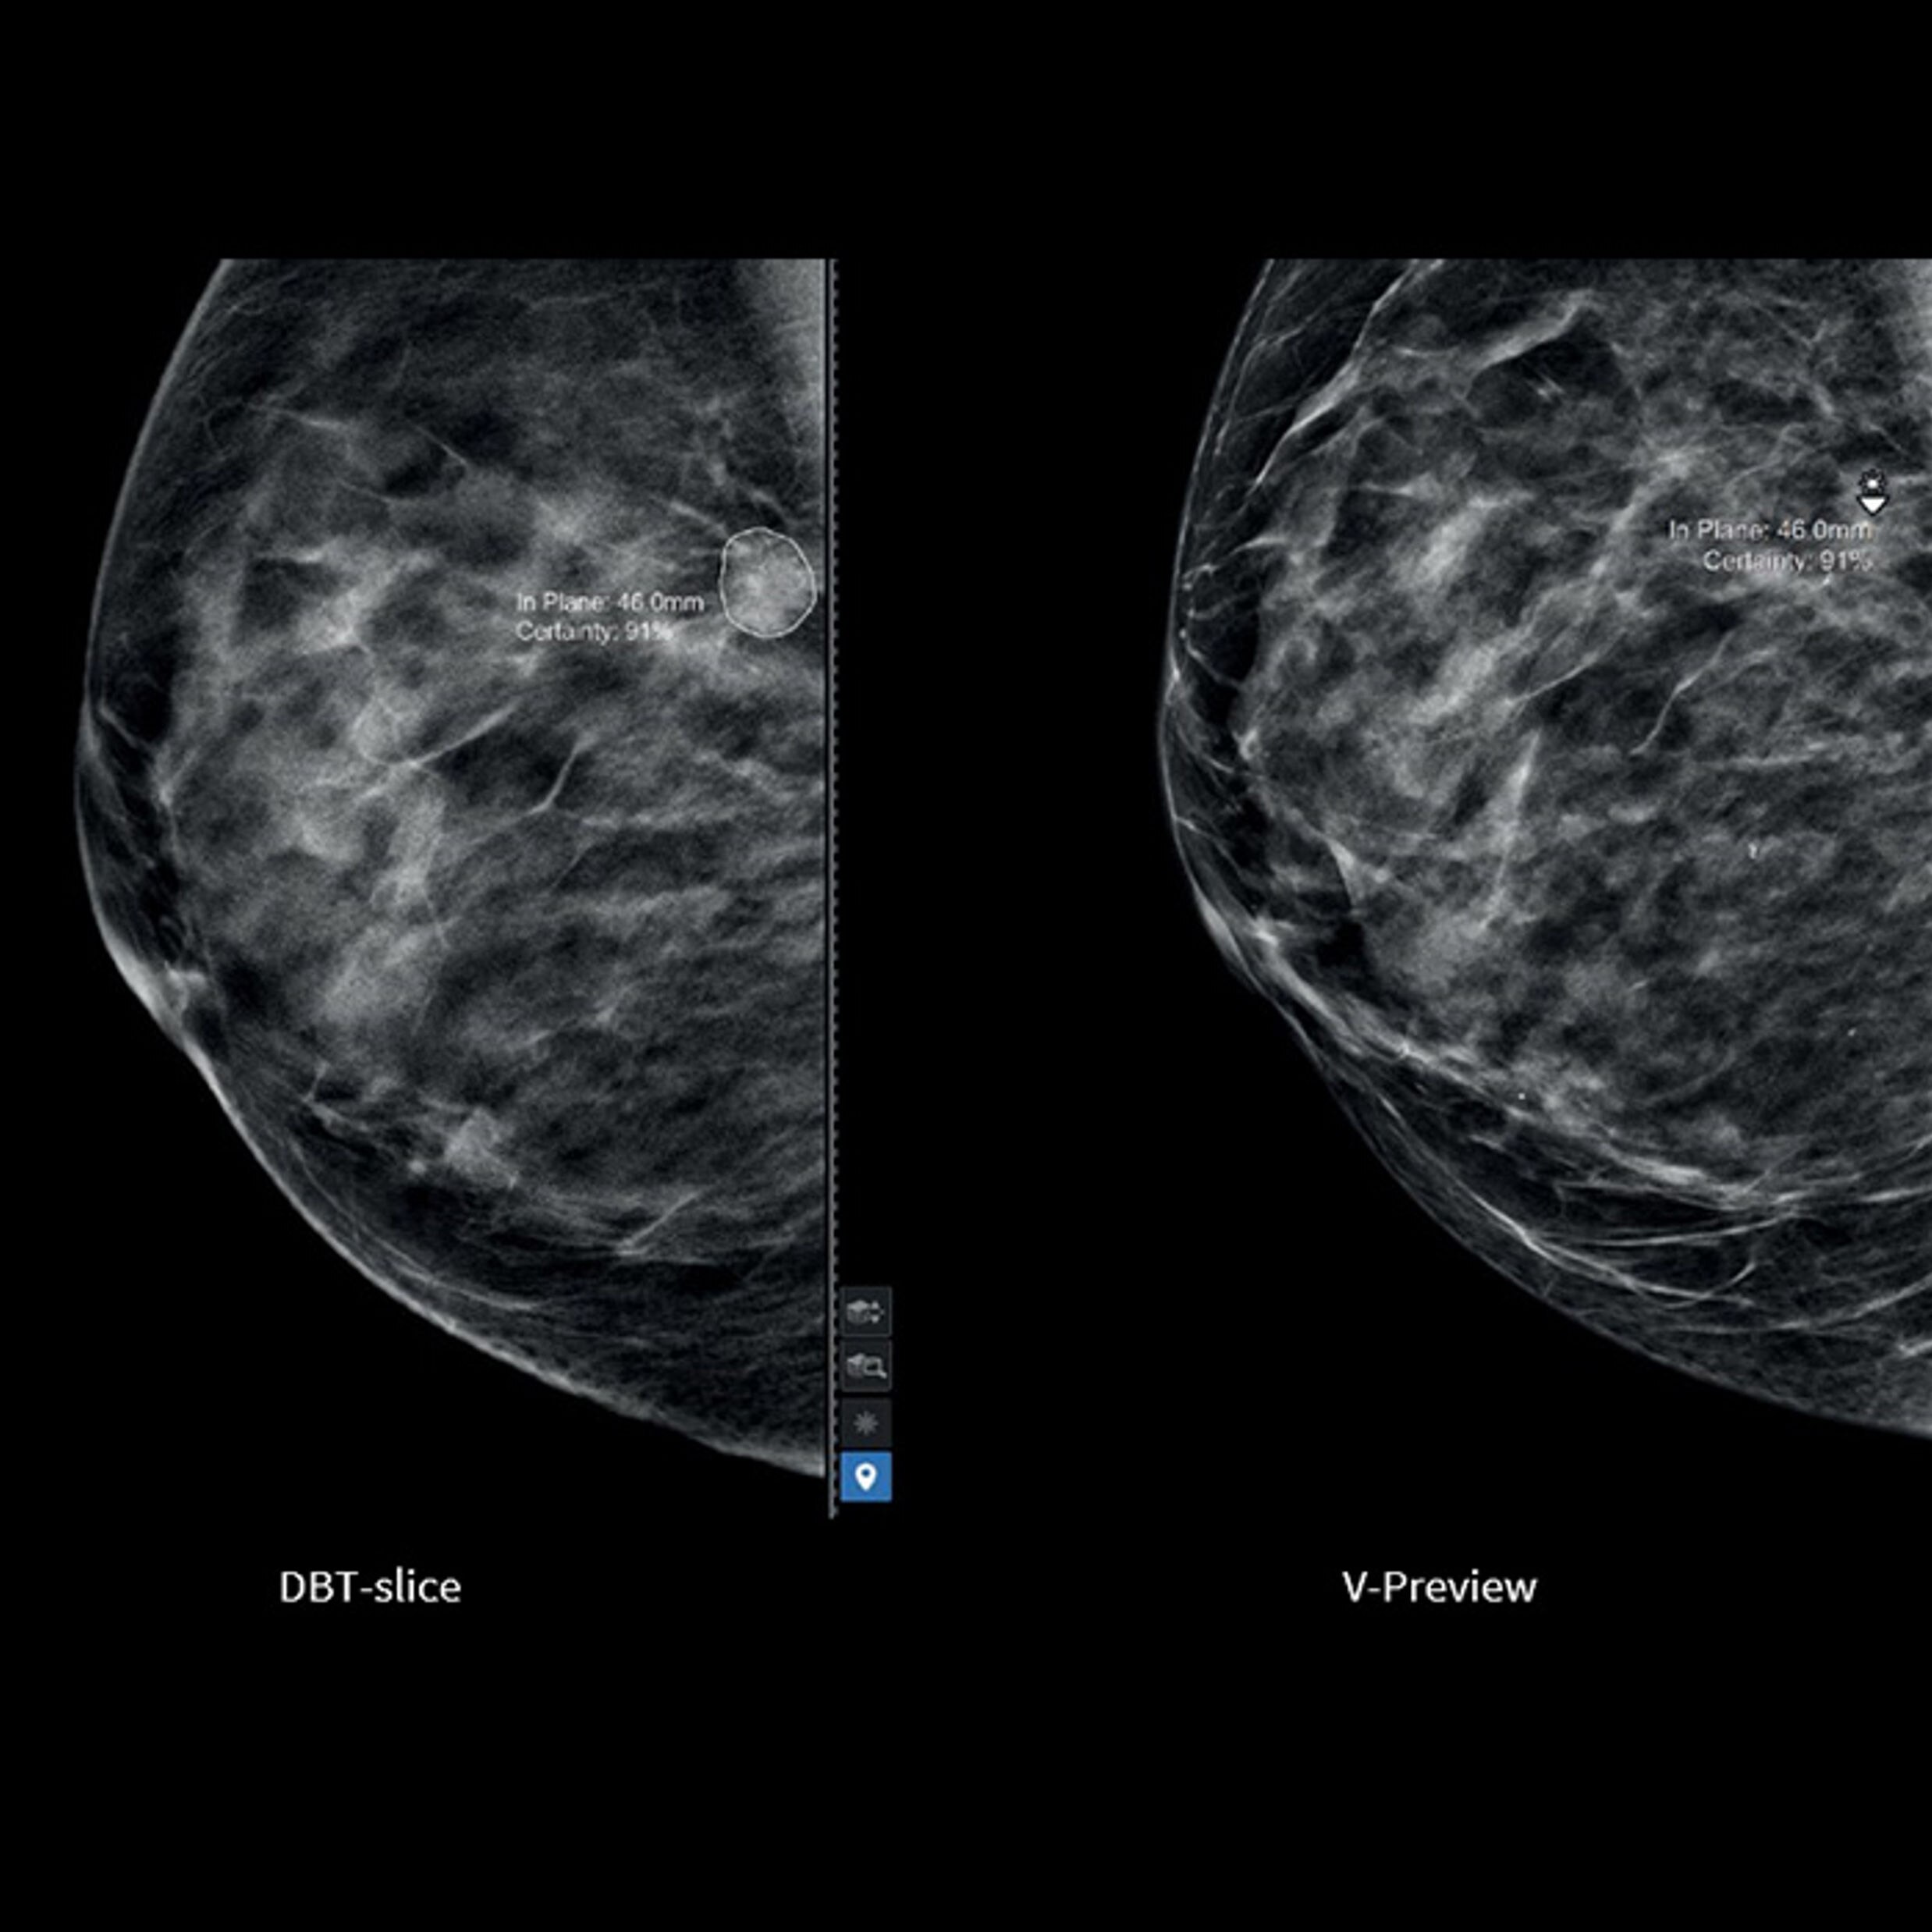

Motion Correction

Clear the way for clear images

Respiratory motion negatively affects about half of all PET/CT procedures. Current gating solutions are cumbersome and take too long to set up. As a result, only a small percentage of overall procedures affected receive motion correction. With MotionFree, Discovery IQ Gen 2 assures that every patient gets the benefit of reduced motion during their exams.

MotionFree is the first-ever digital respiratory motion management solution that eliminates the need for a gating device. It continually monitors respiratory motion in every PET/CT procedure, automatically modifies the scan and then integrates what it learns into the final image in real time. This is the new standard for PET imaging and an essential tool for better outcomes.

• Up to a 30% improvement in quantitation accuracy (SUVmean) compared to non-motion corrected data2

• Up to a 67 percent improvement in lesion volume measurements3

• Avoid adding up to 11 minutes to patient setup time compared to an external gating device4